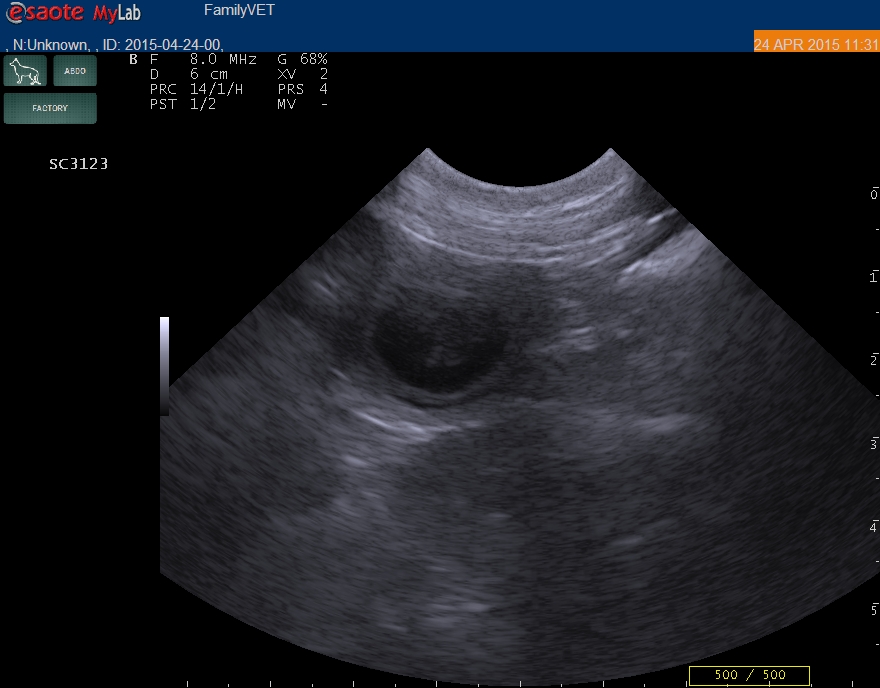

Dnes jsme byli s Farrah ultrazvukovém vyšetření a k naší veliké radosti se potvrdila její březost. Vrh B je tedy na cestě. Na prvních sono snímcích jsme poprvé viděli naše budoucí štěňátka, i když tak zatím nevypadají. Farrynka nám udělala velkou radost a o jednu fotku přidáváme: